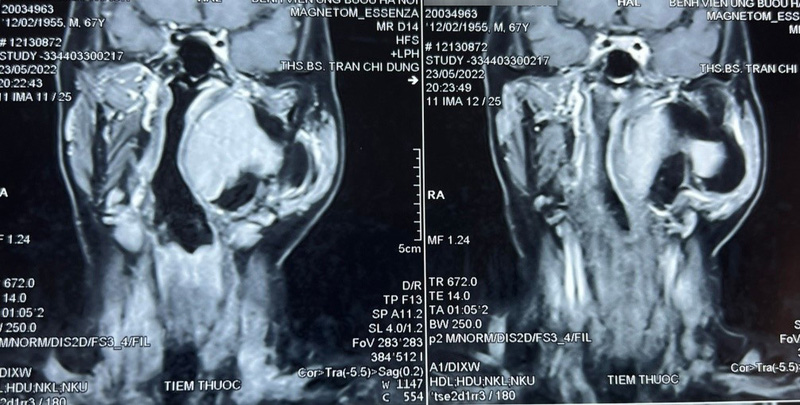

Qua thăm khám và đánh giá, bác sĩ phát hiện một khối u lớn vùng cổ kích thước khoảng 10×8 cm, thuộc khoảng bên họng, trải dài từ nền sọ xuống hạ họng, đẩy lệch thành bên họng vào trong, gồm 2 phần: phần nông nằm dưới tuyến mang tai và phần còn lại nằm sâu hơn. Chẩn đoán sơ bộ ban đầu khối u là lành tính, ranh giới không rõ ràng.

Thông qua hội chẩn, các bác sĩ quyết định tiến hành phẫu thuật sớm lấy bỏ khối u tránh nguy cơ khối u chèn ép vào đường thở, đường ăn, thần kinh, mạch máu và các thành phần liên quan khác. Tiên lượng cuộc mổ là rất khó khăn, đường tiếp cận chính là qua mổ mở từ vùng cổ, phải thực hiện các thao tác phẫu thuật trong không gian hẹp, có thể kết hợp thêm hỗ trợ nội soi.